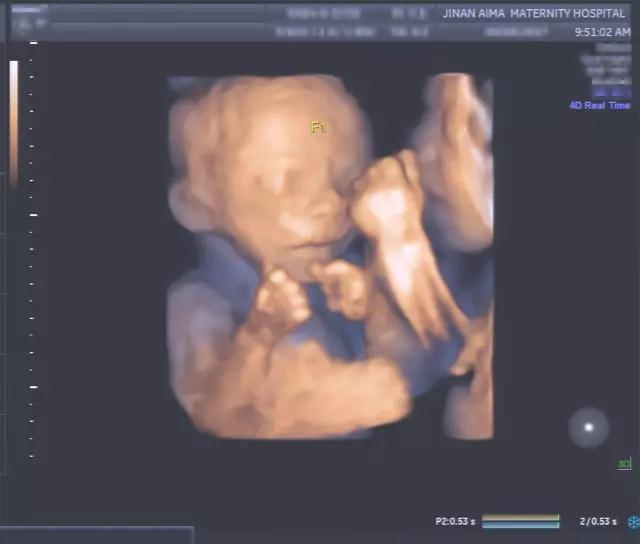

在艾玛妇产四维彩超室

我们看到这样系列

让人“惊讶”的四维彩超(四维彩超)资料

双胞胎宝宝在妈妈的子宫里

是这样“玩耍”的

对双胞胎宝宝面对面

像是在说“悄悄话”

这个温馨的画面

就发生在妈妈的子宫里

被四维彩超记录了下来

能看到双胞胎宝宝互相推挤的胎儿图像

比如双胞胎或三胞胎在子宫里

边抓着对方的手和脸

边互相推挤的过程